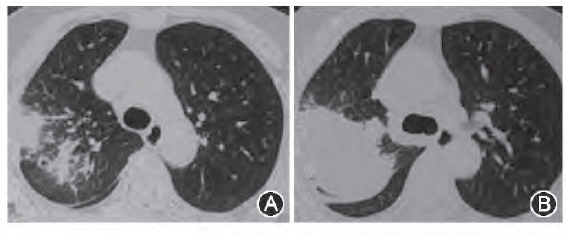

病例7:男性患者,50岁,2009年2月因“咳嗽、咯痰并低热1个月”,胸部cT示肺部多发病变,并伴空洞,痰菌阳性,诊断“肺结核”,给予抗结核治疗1年后复查胸部CT肺内病变无明显变化,继续抗结核治疗3年,痰菌阴转,各项化验如ESR、C反应蛋白等均正常,但肺内病变的影像变化不大,停药。2014年起逐渐出现声嘶、咳嗽、咯痰,无低热、全身乏力等症状,2014年2月经喉镜检测并活检证实为喉结核,入我院后痰菌检查阳性,肺部CT示双肺病变增多,证实结核活动。

病例8:男性患者,30岁,自2009年起问断咳嗽、咯痰,无低热、盗汗、咯血、消瘦等症状。胸部CT示双上肺结节及斑片影,病变密度较高,PPD阳性(+),ESR、C反应蛋白均正常,痰菌阴性,未予抗结核治疗,患者自2014年2月起咳嗽、咯痰明显加重,1个月后出现胸闷、胸痛,偶有低热、盗汗,复查胸部cT示病变明显增多,伴空洞形成,同时出现右侧胸腔积液。

谢汝明:从胸部影像角度,国内外文献判断结核病变活动性主要集中于3点:(1)渗出性病灶;(2)是否伴有空洞形成;(3)播散性病变的影像存在,如树芽征等。从病例7停药时的肺部CT可见斑片结节阴影,有树芽征表现,同时有空洞存在,停药时的病变存在活动眭病变。